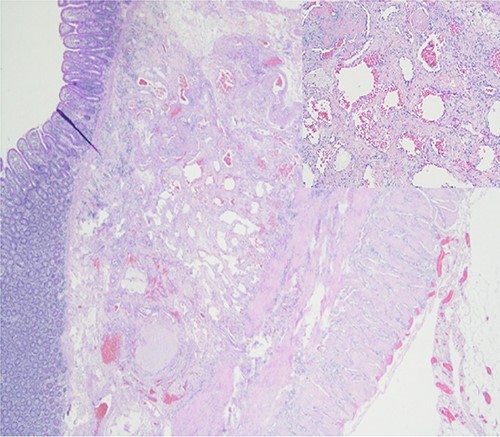

Further episodes of rectal bleeding were noticed the following day, and the hemoglobin level dropped significantly, requiring blood transfusions. An urgent computed tomography (CT) mesenteric angiography was performed, which demonstrated the extravasation of contrast in a segment of distal ileum (Fig. 1), ~30 cm from the ileocecal valve, suspicious for angiodysplasia. She subsequently underwent a laparoscopy, which was converted into a lower-midline laparotomy due to dense omental adhesions secondary to prior appendectomy and cesarean sections. After adhesiolysis, small bowel was thoroughly examined. The terminal ileum contained blood, while proximal small bowel appeared unremarkable. About 30 cm from the ileocecal valve, a small transmural lesion was noticed, which was red and blanching in appearance (Fig. 2). A segmental resection of ileum was performed, and the specimen was cut open to demonstrate the luminal aspect of AVM (Fig. 3). A primary anastomosis was performed. Histology showed a small, non- encapsulated nodule, composed of complex clusters of thin and thick-walled blood vessels, abnormally located in the submucosa (Fig. 4). Post-operatively, the patient had an uneventful recovery and was discharged home well after 4 days.

Resected ileal segment showing luminal aspect of AVM, indicated by white arrow.